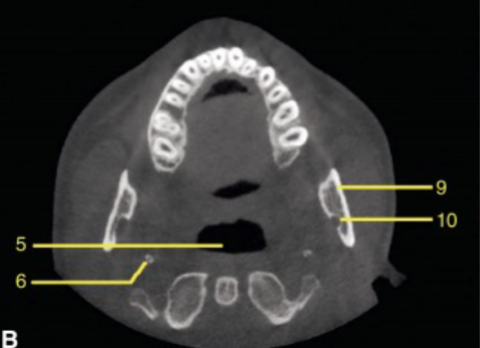

mandible

which arch is this

apical of roots

at what level is this